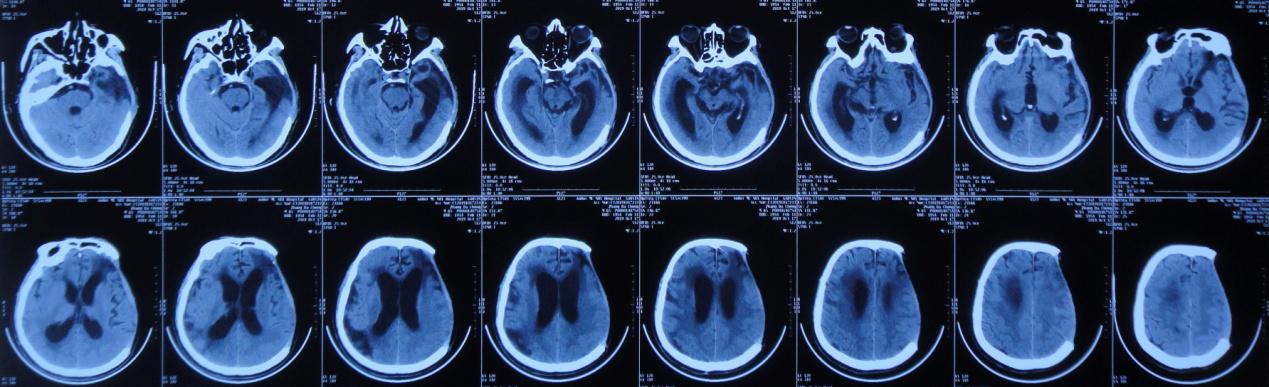

左颞叶血肿清除+去骨瓣减压术后第45天,即2019年8月24日,复查头颅CT( 图-3 )示颅脑术后改变,脑室基本“正常”,脑室周围稍水肿。

图-3: 2019年8月24日头颅CT

左颞叶血肿清除+去骨瓣减压术后第52天,即2019年8月31日,复查头颅CT( 图-4 )示脑室较前无明显变化,脑室周围仍稍水肿。

图-4: 2019年8月31日头颅CT

左颞叶血肿清除+去骨瓣减压术后第63天,即2019年9月11日患者言语较前清晰,单侧搀扶下可行走,复查头颅CT( 图-5 )(双颞增大)脑室较前仍无明显变化,但脑室周围水肿稍加重。

图-5: 2019年9月11日头颅CT

左颞叶血肿清除+去骨瓣减压术后第99天,即2019年10月17日患者言语基本清晰,可独立缓慢行走,复查头颅CT( 图-6 )示:颅脑术后改变,脑室较前无变化,脑室周围水肿较前无变化。

图-6: 2019年10月17日头颅CT